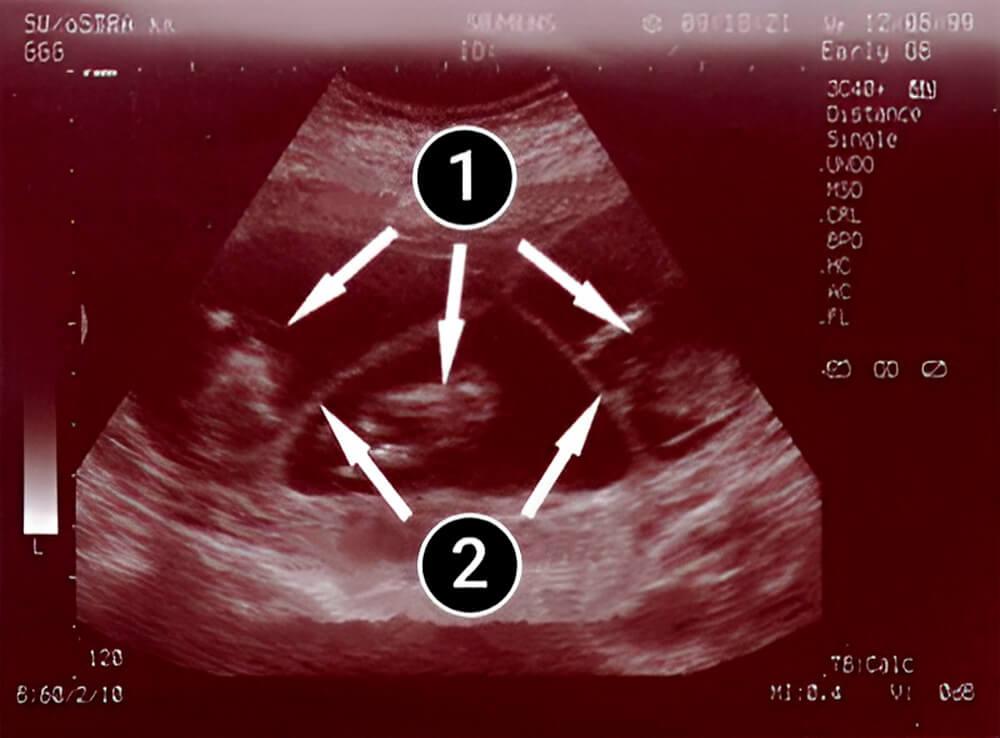

La segunda imagen muestra una visión menos común: ¡trillizos! Tres bebés crecen juntos en el útero, cada uno tiene su propio saco amniótico y comparten una placenta. El bebé de enmedio es más visible que sus hermanos y destacan su cabeza y piernas.

tres bebes

saco amniótico